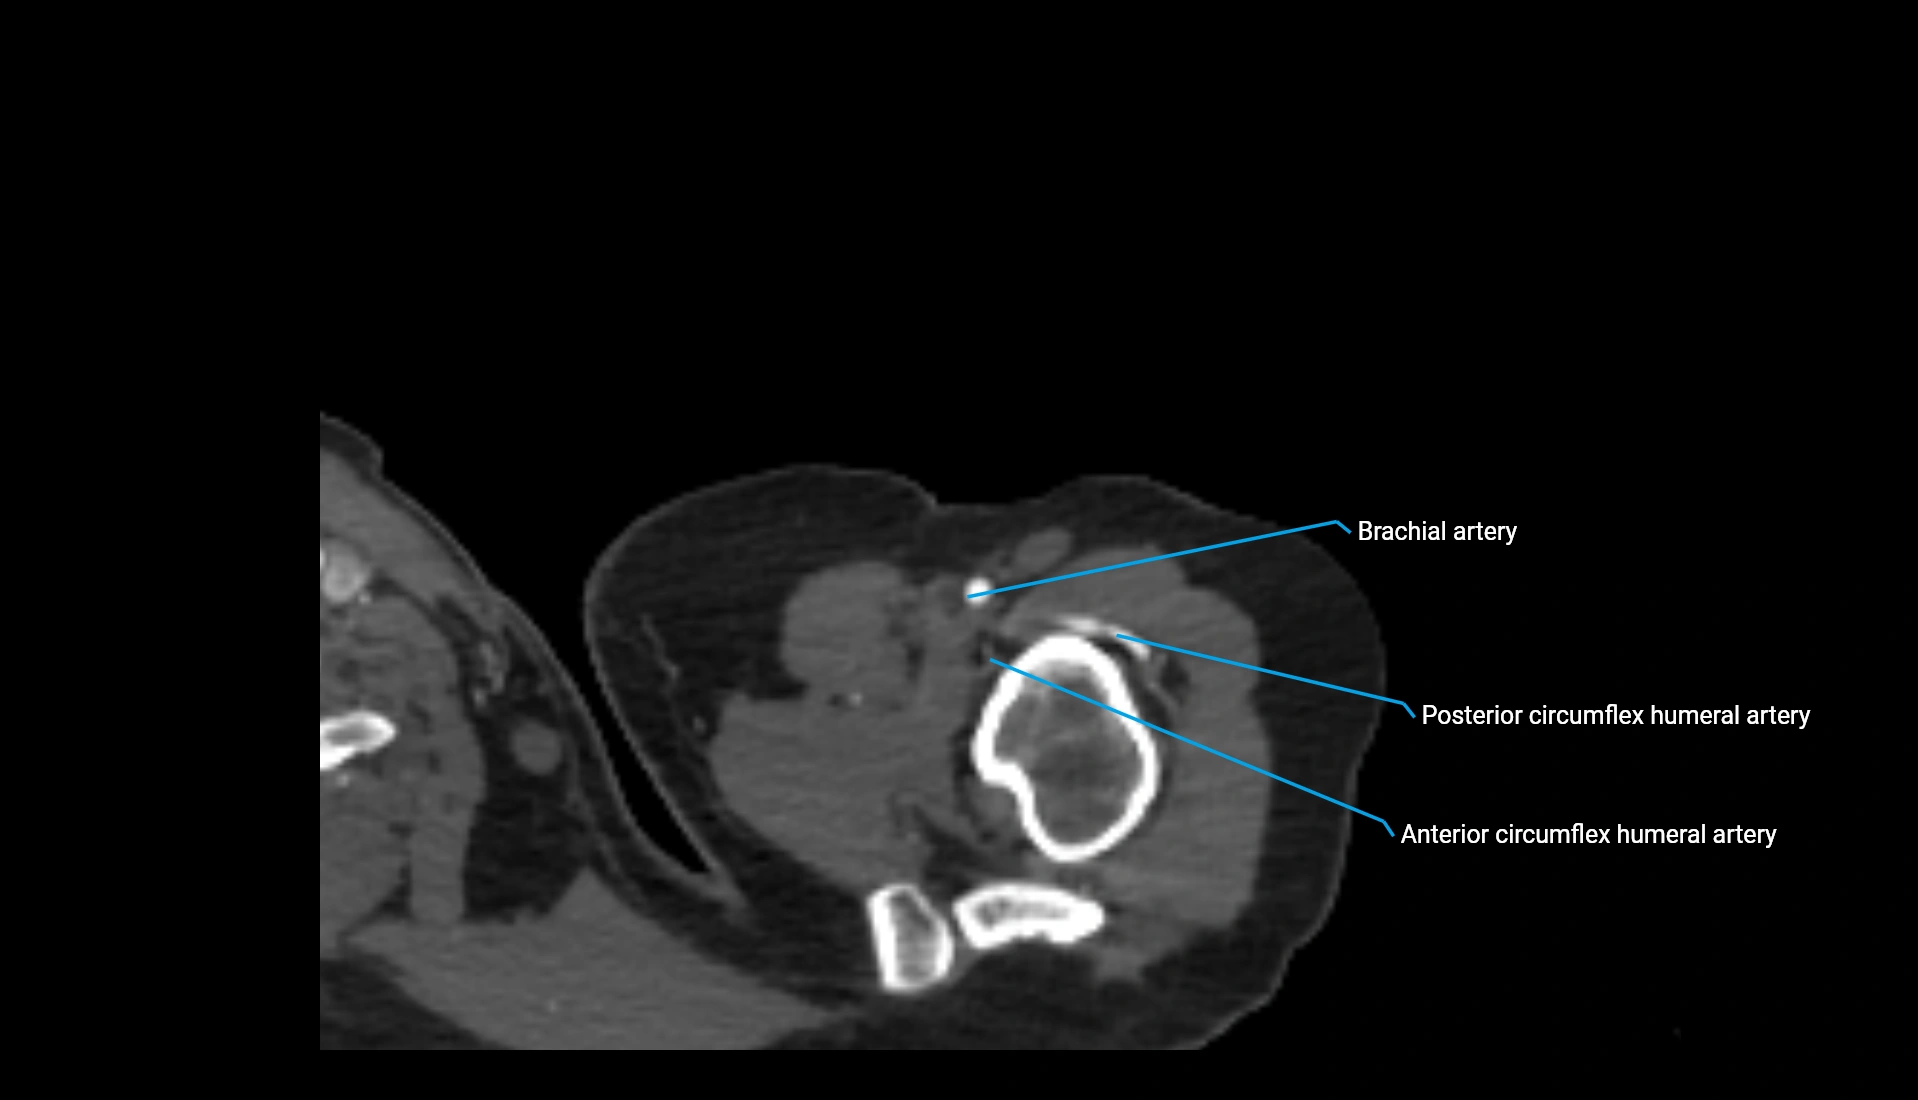

CT Appearance

Non-Contrast CT:

• Cortex: High-density, sharply defined

• Subchondral bone: Dense cancellous matrix

• Articular surface: Smooth concave contour articulating with the capitellum

• Excellent for evaluating bone integrity, alignment, and subtle fractures

Post-Contrast CT:

• Bone: No enhancement

• Joint capsule and synovium: Mild enhancement outlining the joint

• Improves contrast between soft tissues and bony margins

• Useful in detecting subtle joint abnormalities or postoperative changes